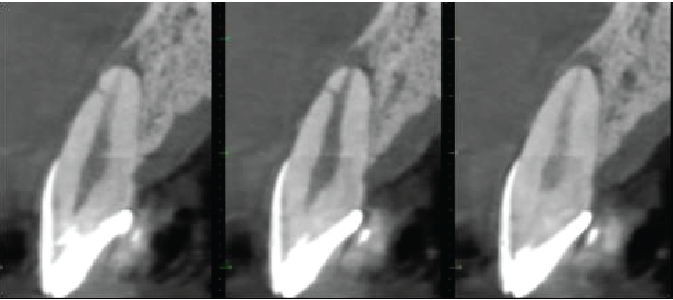

Cross sectional images of UL2

Mesio-distal

Labio-palatal

Oblique (mesio-labial to distopalatal) to show lateral canal

The UL2 has a heavily restored crown. Dens invaginatus anomaly seen (Oehler type I). The root canal is patent. Projections of the root canal pass mesially and distally around the deep part of the invagination and presumably meet on the palatal side. There is also a lateral canal 2.5mm from the apex directed mesiolabially. There is a 7.5mm maximum diameter periapical radiolucency, extending along the mesial side of the root almost to the crestal bone level. The apex is flattened, indicating some apical inflammatory resorption.